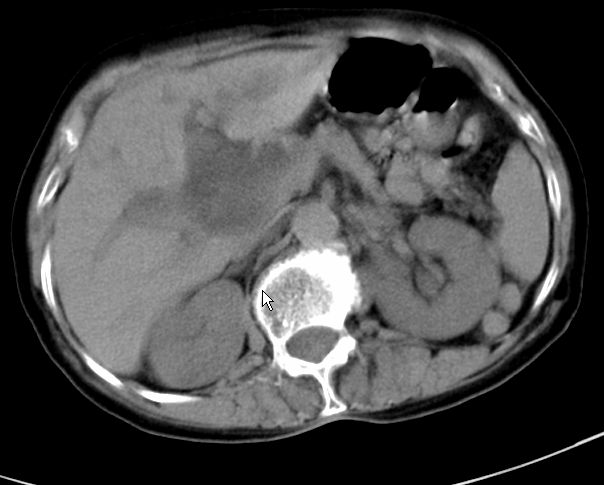

以下是引用zjzjr在2008-12-16 12:49:00的发言:[br]肝内外胆管全程扩张,胆囊明显增大,未见占位征像.建议mrcp.

以下是引用jiangjing在2008-12-16 13:19:00的发言:[br]肝内外胆管全程扩张,胆囊明显增大,扩张胆总管下段径较中上段小,未见胰管扩张,提示胆总管远端梗阻伴感染.建议增强及mrcp 检查

以下是引用朱亮在2008-12-16 12:54:00的发言:[br]胆总管远端应薄层扫描 胆总管逐渐变细 考虑胆系慢性炎症